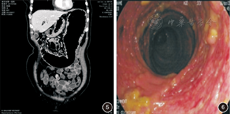

例3 患者女,60岁,因"反复便秘二十余年,腹部不适伴发热20 d"入院。患者二十余年来间断反复便秘,20 d前出现腹部不适、纳差伴发热,体温波动于37℃~38℃。每日排便1次,性状正常。入院查体:左上腹压之不适感明显,叩诊左侧鼓音增强,肠鸣音正常。血常规:WBC 7.28×109/L、N 69.0%、Plt 385×109/L;粪便常规+隐血、粪培养均正常;血沉25 mm/h;C反应蛋白79 mg/L;T-spot(-)。腹部CT示横结肠明显扩张(图5),未见小肠及肠道血供异常。胃镜未见异常;肠镜示横结肠节段性黏膜异常,见充血糜烂、浅溃疡形成,局部见假息肉样隆起及黏膜桥,两端肠管黏膜均正常,病灶与正常黏膜分界清晰(图6)。肠镜病理示黏膜慢性炎、炎性肉芽组织;抗酸染色阴性;免疫组化检测示巨细胞病毒抗体阳性。直肠下端正常黏膜活检示肠壁神经节可见。更昔洛韦治疗15 d后,体温正常,予出院。随访3年至今患者情况良好。出院诊断为"巨细胞病毒性肠炎,特发性巨结肠"。

例3中患者的情况稍复杂。除巨结肠外患者同时伴有巨细胞病毒性肠炎,两者之间孰因孰果?考虑到该患者二十余年来反复便秘而伴有腹部不适、发热仅20 d,且经抗病毒治疗后病情可以缓解,故认为该患者在特发性巨结肠的基础上合并了巨细胞病毒感染的可能性较大。